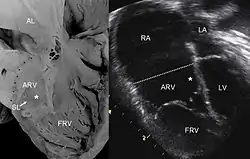

![]() عينة مرضية لصورة تحت الأمواج الصوتية لقلب مصاب بشذوذ إبشتاين. المختصرات: RA: الأذين الأيمن ARV:البطين الأيمن متأثرا بالأذين FRV: البطين الأيمن الوظيفي AL:الوريقة الأمامية SL: وريقة حاجزية LA: الأذين الأيسر LV: البطين الأيسر عينة مرضية لصورة تحت الأمواج الصوتية لقلب مصاب بشذوذ إبشتاين. المختصرات: RA: الأذين الأيمن ARV:البطين الأيمن متأثرا بالأذين FRV: البطين الأيمن الوظيفي AL:الوريقة الأمامية SL: وريقة حاجزية LA: الأذين الأيسر LV: البطين الأيسر | |